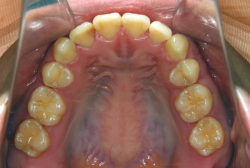

凸凹な歯並びのことを叢生といいます。矯正歯科に来院する患者様の主訴の中で、最も多いのが「配列の凸凹を真っ直ぐにしたい」というものです。歯の大きさと顎の大きさの調和がとれていないことが原因です。

凸凹を主体としたケースの場合、当院の平均治療期間は18ヶ月ですので、このケースは少し長めに経過しました。理由の一つは凸凹の程度がかなり重症だったと言うことですが、もう一つは、右下第2大臼歯が45度くらい前傾していたため、それを整直化させるために時間を要したと考えています。いずれにしても最終結果は大変よい状態と思います。

治療前は並びが乱れて見た目が悪いというのはもちろん問題ですが、歯科医学的に一番困るのは噛み合わせが悪いという点です。上下の犬歯(3番目の歯)は、上下的に離れた位置にあるため接触することができません。つまり歯としては存在していても、歯としては機能していないということです。